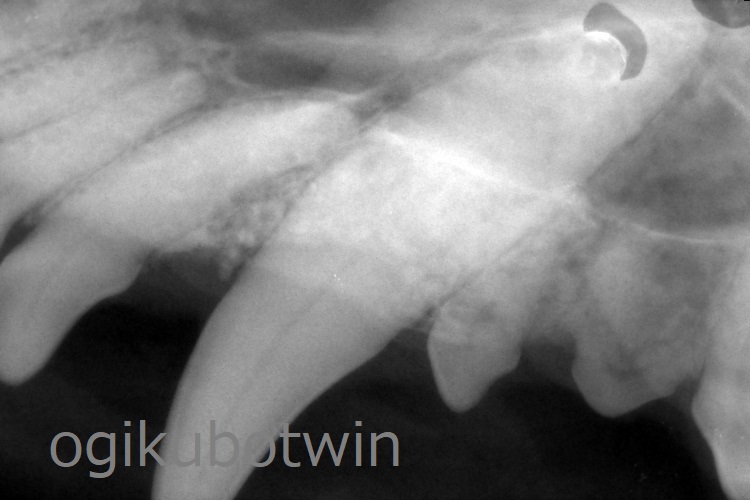

全身麻酔下で歯科レントゲン検査を行い、歯の状況を確認し手術を行いました。

両側下顎の第一後臼歯(奥歯)は近心、遠心ともに歯周病が進行していいたため、温存するためにその両側の第四前臼歯(奥歯)と第二後臼歯(奥歯)を抜歯しました。

両側の上顎犬歯は歯周ポケットが深くなっていましたが、鼻腔まで到達していないことが確認できたので再生治療を行いました。

両側の犬歯ともに軟組織を除去して、骨を露出させた状態でエムドゲインとβ-TCP(骨補填剤)を用いて充填させました。

9か月後に鎮静下にてレントゲンを撮影し、再生治療の経過を確認します。

9か月後の検診時、犬歯の歯周ポケットは浅くなっており、経過良好です。